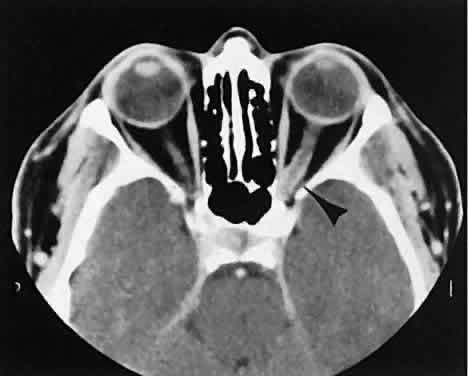

The muscle belly has a smooth contour with no edema of the adjacent orbital fat. We recently evaluated a patient with a referral diagnosis of Graves' orbitopathy. The patient was euthyroid but had severe orbital congestion typical of advanced Graves' orbitopathy. Imaging showed “dirty” orbital fat and lateral rectus muscle morphology that seemed atypical (Fig. 8). Biopsy specimen results showed a low-grade lymphoma. Hypertrophy of the medial rectus muscle can cause the medial wall to bow in toward the ethmoidal sinus from the chronic effects of pressure on the bone. The hypertrophied muscles also can give rise to a compressive optic neuropathy in the orbital apex as the enlarged muscles take their origin from the anulus of Zinn. Axial views of the apex show an apparent mass if the inferior rectus muscle is enlarged. It is imperative that additional views, sagittal or preferably coronal, be obtained to show the true nature of this apparent mass. Intracranial fat prolapse, seen by CT, may be another sign of optic neuropathy.44 An optic neuropathy also can be seen with relatively normal-sized EOM. An expanded fat compartment with optic nerve stretch has been associated with an optic neuropathy.45,46

Fig. 8. Low-grade lymphoma confined to orbit mistaken for Graves' ophthalmopathy in a 65-year-old man. A. On the axial view, orbital fat appears “dirty” with marked increase in soft tissue stranding. Muscles do not have a smooth appearance, lateral rectus muscles have lumpy appearance (arrow), and both lateral rectus muscles are disproportionately large for what typically is seen in Graves' orbitopathy. B. Coronal view also shows dirty orbital fat. Note left inferior rectus, which is small (arrowhead), and also is atypical in Graves' orbitopathy when there is enlargement of the other extraocular muscles.